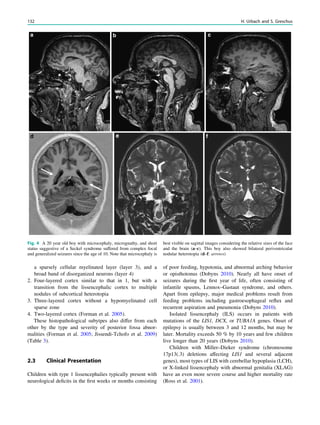

Coronal slices are almost always angulated perpendicular to

the hippocampal long axis. To obtain this angulation, we

start with a sagittal sequence, typically a 3D T1-weighted

gradient echo sequence, and use a paramedian slice

displaying the hippocampal long axis for planning. To avoid

tilting in the coronal plane, coronal slices are also adjusted